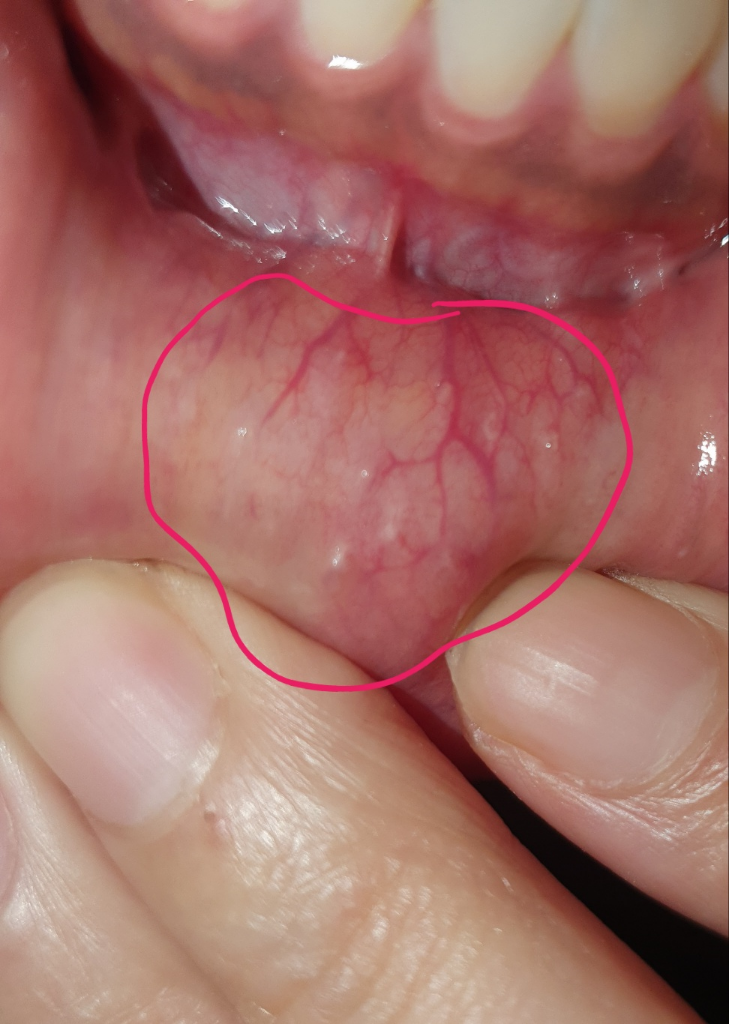

구강 점막에 유분이 있거나 한다면 부분적으로 돌기처럼 나올 수 있습니다 크게 문제가 되지 않을 것으로 생각되나 자세한 확인을 위해서 치과에서 진료를 받아 보세요

문제가 잇는건 아닙니다. 아프거나 그렇지 않으면 문제가 잇거나 그런건 아니니 걱정하지 않으셔도 될것같습니다.

크게 병적인 것은 아닙니다. 사진상 보이는 것들은 입술 피지선 등의 정상 해부학적 구조로 생각됩니다.